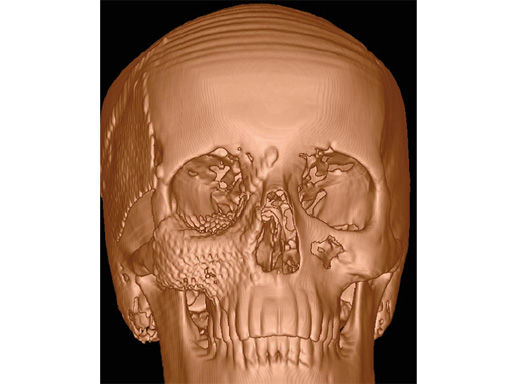

This sterile artificial skull model is an approximation of the average craniofacial anatomy, originating from data from up to 2000 analyzed CT scans. These scans were used to develop the matrix midface preformed orbital plates and the matrix mandible preformed reconstruction plates (Fig 2), launched in 2008 and 2009, respectively. The manufacturing material is polyphenylsulphone, which allows the skull to be steam sterilizable, reusable, cleanable, and biocompatible.

Case 2: A 19-year-old woman had an extended sinunasal carcinoma in the right maxillary sinus area. fig 2 shows four views of the virtual preplanned computer-aided design; the reconstruction is represented in pink (fig 2a). The three remaining multiplanar views show the overlapping images of the virtual preplanned reconstruction (pink) and reconstruction result performed by using two individualized 3-D meshes (one for a three-wall-reconstruction of the orbit and one for reconstructing the right midfacial prominences).